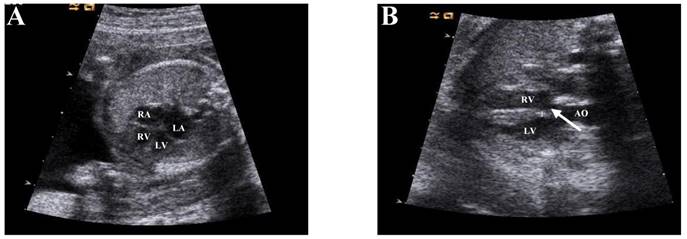

This experiment adopts a case-control study design. To examine the different expression of circRNA, we conducted high-throughput microarray technology to detect heart tissue divided into two different groups: VSD and normal (n=3 tissues per groups). We collected cardiac tissue from aborted fetus at 24-28 weeks of gestation depending on embryos diagnosed by ultrasonography (Figure 1). In order to exclude the interference of non-research purposes related factors, we excluded the tissues collected from whose mother had other diseases, and the embryos had genetic disorders, such as 21- trisomy syndrome. To validate the microarray, we randomly selected 5 circRNAs (hsa_circRNA_002086, hsa_circRNA_007878, hsa_circRNA_100709, hsa_circRNA_101965, hsa_circRNA_402565) and examined its expression in 12 pairs of fetal heart tissue samples at 24-28 week of gestation by quantitative reverse transcription-polymerase chain reaction (qRT-PCR).

Enrollment occurred from January to June 2016 at the Obstetrics and Gynecology Hospital affiliated of Nanjing Medical University Department of Family Planning. Prenatal ultrasound diagnosis of VSD for aborted fetuses, and fetal abortion with VSD were confirmed by anatomy, and are not associated with other malformations. Controls included aborted fetuses whose prenatal diagnosis were no abnormal genotype and were confirmed to lack VSD or other cardiac malformation. The results of imaging diagnosis are shown in Figure 1.

Figure 1

Echocardiographic diagnosis of fetal heart. a. The four chambers of the heart of a normal fetus (Arrow position). b: Resting diagram of Ventricular Septal Defect (VSD) (Arrow position). Note RV, right ventricle; LV, left ventricle; RA, right atrium; LA, left atrium; AO, aorta.